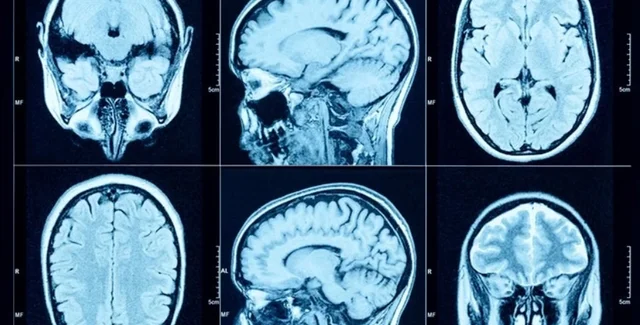

В исследовании принимали участие добровольцы в возрасте от 40 до 69 лет из Биобанка Соединенного Королевства (БСК) в период с 2006 по 2010 год. Некоторые участники прошли визуализацию мозга, включая магнитно-резонансную томографию (МРТ).

Диагностические критерии подагры были определены алгоритмически на основе базовой оценки БСК. Уровень уратов в сыворотке крови измерялся в начале исследования.Используя различные методы МРТ, исследователи проанализировали структуру мозга, используя 2 138 различных суммарных фенотипов, включая объем серого вещества, диффузионную МРТ и МРТ с взвешенной восприимчивостью. Пространственное распределение связи между подагрой и объемом серого вещества по всему мозгу определялось с помощью воксельной морфометрии на основе библиотеки программного обеспечения.

В исследовании также проводилась линейная оценка МРТ с использованием сводной статистики у европейских участников для изучения причинно-следственных связей между подагрой и структурой мозга. Согласование вариантов обеспечило точное описание корреляции между однонуклеотидными полиморфизмами (ОНП) и подагрой, а также ОНП и исходами. В исследование было включено в общей сложности 11 735 участников с подагрой, из которых 1 165 прошли визуализацию мозга. Период наблюдения показал, что пациенты с подагрой умирали в два раза чаще по сравнению с контрольной группой, причем у 3 126 участников отмечалось слабоумие.

Уровни урата были обратно пропорционально связаны с различными объемами мозга, включая общий объем мозга, объем серого вещества, объем белого вещества и высокий объем спинномозговой жидкости. Было установлено, что подагра оказывает такое же влияние на глобальный объем серого вещества, как и старение на два года.

Конкретные области мозга, на которые подагра повлияла, включали мозжечок, средний мозг и области белого вещества, такие как свод мозга. Подагра и высокий уровень уратов в сыворотке крови были также связаны с повышенным отложением железа в структурах базальных ганглиев, а именно в двустороннем путамене и хвосте. Это накопление железа может быть вызвано воспалением, связанным с подагрой, или нарушением выведения железа с мочой.

Эти результаты представляют собой первое доказательство связи подагры с нейродегенеративными заболеваниями с помощью нейровизуализационных исследований. Однако классические визуализационные маркеры болезни Альцгеймера или сосудистой деменции не были обнаружены в мозге пациентов с подагрой.